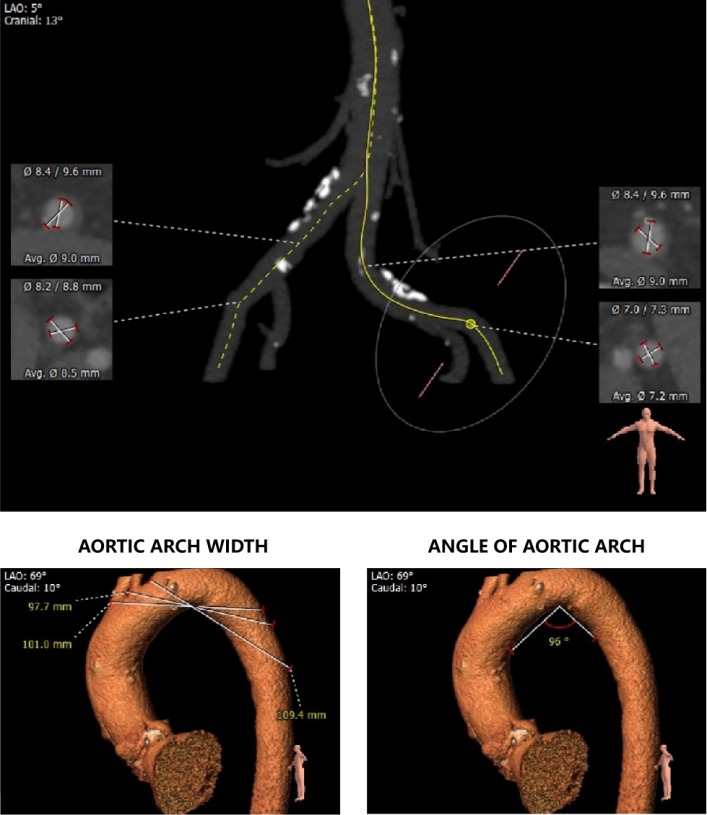

外周血管及主动脉弓解剖:

③患者瓣环水平夹角较大,近横位心,输送器过弓存在一定难度。

③患者近横位心,术中应加以snare辅助输送器过弓。